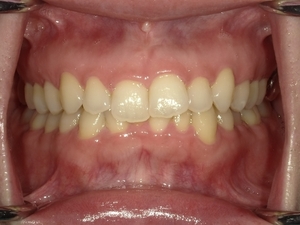

ガタガタとした歯並びや八重歯(叢生)CASE66